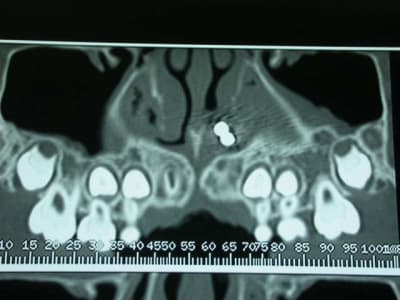

Merci pour la cas clinique kalif...on voit bien la chaînette sur la pano par contre la règle ne devait pas etre radio-opaque ;-)

l'objet: une petite chainette boule métallique (celles qui sont accrochées à certains vetements et qu'on retrouve sur les bouchons de baignoire) complétement oxydée (noir de chez noir, avec diminution du diametre de certaines boules) .

temps de séjour estimé dans les fn: 4-5 ans

La maman de zoe vient en consultation, pour un contrôle semestrielle. Elle est enceinte de 8 mois, se porte bien , et rien de particulier ne doit être entrepris avant la fin de la grossesse. En fin de rendez-vous, elle me demande de jeter un œil sur Zoe. La petite agée de 9ans et demi présente une jolie classe III osseuse. J’en profite pour lui faire une panoramique. Là, à ce stade, vous avez tous vu le résultat. Je vérifie qu’il ne reste pas une barrette oubliée ou autre (nada), et préfère effectuer une nouvelle pano. Même résultat.

Je décide donc de faire réaliser un scanner et là c’est nouveau pour vous.

Une fois le scanner réalisé, je vois bien qu’il s’agit d’un objet composé de boules et l’adresse illico à son orl. Il la reçoit dans la foulée, et au vu du scanner, se refuse d’intervenir de peur de renvoyer plus loin l’objet. A son tour, il l’adresse à un hopital spécialisé enfants (Robert Debré). Au service ORL, ils tentent de retirer l’objet avec une pince (comme Dr House le faisait dans un épisode) et rien de neuf, aucune progression.